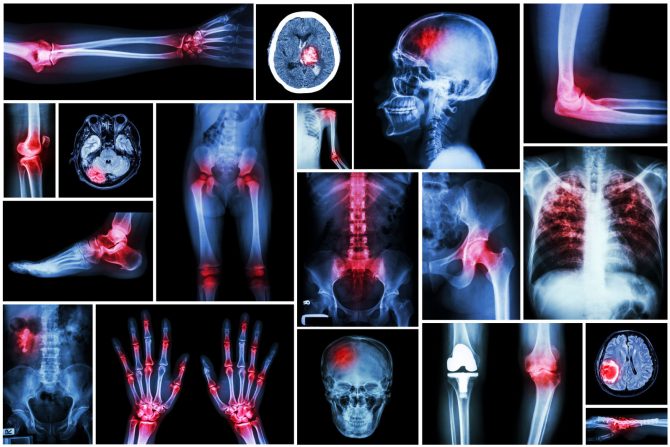

Reumatoidni artritis uzrokuje upalu zglobova i bol i javlja se kada imuni sistem više ne funkcioniše dobro i počinje da napada sluznicu zglobova, zvanu sinovija. Bolest obično zahvata  ruke, kolena ili gležnjeve i obično isti zglob na obe strane tela, kao što su obe ruke ili oba kolena. Ali, ponekad reumatoidni artritis izaziva probleme i u drugim delovima tela, kao što su oči, srce i  pluća.

Reumatoidni artritis ne utiče i oštećuje samo zglobove, već može da ošteti i tkivo koje okružuje zglobove, oči, srce i pluća. Komplikacije na plućima izazvane reumatoidnim artritisom mogu da budu ozbiljne i čak dovedu do smrti. Istraživanje objavljeno u  European Respiratory Review pokazalo je da oštećenje sluznice pluća ili pleure može da se javi kod oko 70 procenata svih ljudi sa reumatoidnim artritisom, ali samo 3 do 5 procenata njih ima simptome. Skoro 10 odsto ljudi koji žive sa reumatoidnim artritisom takođe će razviti intersticijsku bolest pluća ili ožiljke na plućnom tkivu, napominju stručnjaci.

Intersticijalna bolest pluća, na primer, dovodi se u vezu sa reumatoidnim artritisom i jedna je od najozbiljnijih plućnih komplikacija za osobe sa reumatoidnim artritisom. Ova bolest se teško otkriva, ali se javlja kada se plućno tkivo upali i na kraju se jave ožiljci. Francuska studija objavljena u Arthritis and Rheumatology u novembru 2022. pokazala je da je prevalencija subkliničke (bez simptoma) intersticijalne bolesti pluća nakon srednjeg trajanja reumatoidnog  artritisa od 13 godina bila 19 procenata, što pokazuje da razvoj intersticijalne bolesti pluća uz postojanje reumatoidnog artritisom nije redak slučaj.

Vremenom, reumatoidni artritis može da dovede do oštećenja plućnog tkiva, što može da uzrokuje stanje poznato kao plućna fibroza i izaziva ozbiljne probleme sa disanjem. Plućno tkivo tada postaje debelo i ožiljno, što otežava apsorpciju kiseonika u krvotok. Plućna fibroza je vrsta intersticijske bolesti pluća. To je deo mnogih različitih stanja pluća koja mogu da izazovu upalu u vazdušnim kesama pluća, kao i u plućnom tkivu i vazdušnom prostoru između kesa. Ožiljci mogu da blokiraju kretanje kiseonika iz pluća u krv što zauzvrat može da dovede do kratkog daha, posebno uz aktivnosti koje zahtevaju napor.